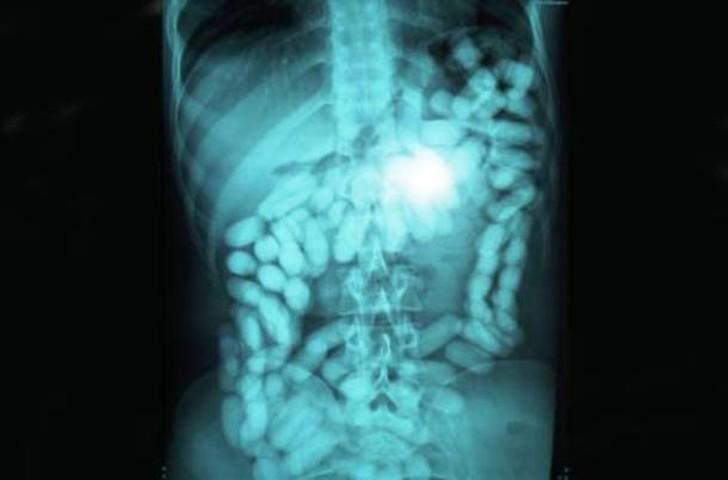

23. Метамфетамины.